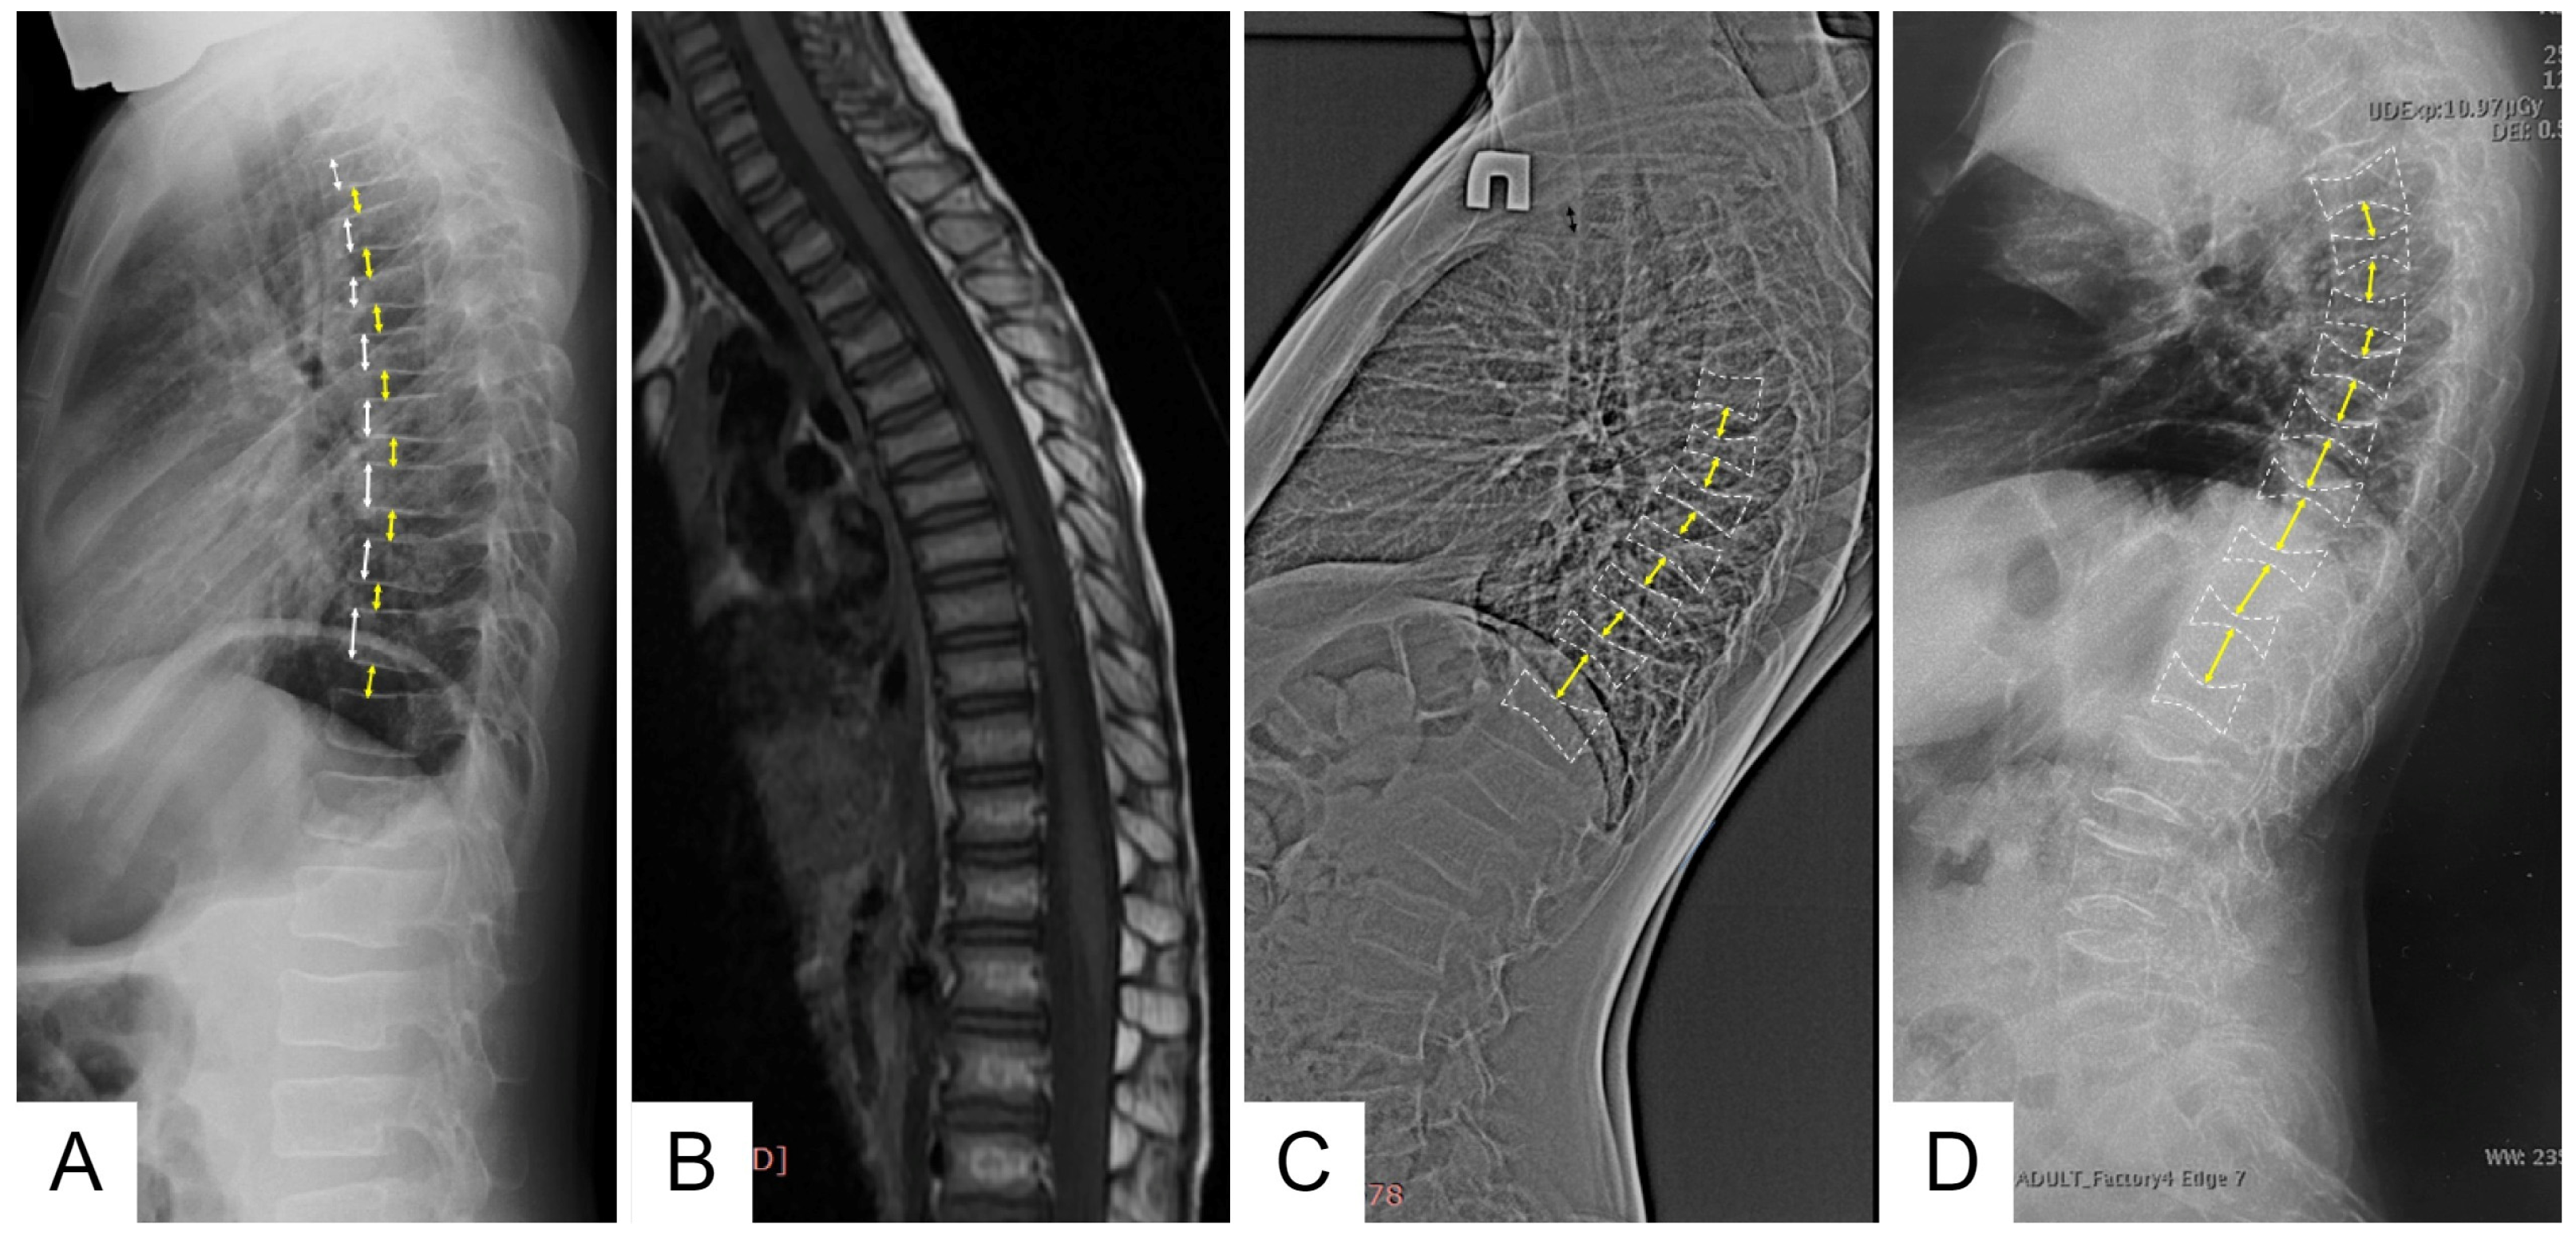

Family 1 is Belarusian and has five affected members in three generations. Proband (III-4) is a 6-year-old boy who started to complain (pointed to where it hurt) of lower back pain from the age of 1 year 7 months, according to his parents. This pain usually lasted from 2 weeks to 1 month and limited the patient’s physical activity, as he was afraid to walk the stairs. Taking into account the increasing lower back pain, an MRI of the thoracolumbar spine was performed at the age of 4 years, which revealed signs of compression fractures of the C7, Th 2-8 vertebral bodies (Figure 2).

Control X-ray densitometry at the age of 6 showed positive dynamics: the BMD of the lumbar spine was 0.357 g/cm2, Z-criterion was −1.9. An X-ray examination of the spine at the age of 6 years revealed diffuse rarefaction of the bone pattern of the vertebrae and a biconcave shape of the thoracic vertebral bodies (Figure 2).

According to the results of the densitometry, all affected family members were diagnosed with severe osteoporosis, and an X-ray examination of the spine revealed signs of compression fractures of the vertebral bodies (Figure 2).

An X-ray examination of the thoracolumbar spine revealed a biconcave appearance of the vertebrae and a wedge-shaped deformity of the vertebral bodies at the entire level of the thoracolumbar spine (Figure 2). During bone scintigraphy of the skeletal system in a 30-year-old individual, no metabolically active zones were detected, which are often found in patients with osteogenesis imperfecta, even outside fracture zones and bone calluses.

Figure 2. Lateral views of the thoracic and upper lumbar spine of the patients of different ages: radiograph of the 6 y.o. boy (F1 III-4) (A)—decreased height and anterior wedging of the vertebral bodies (white arrows), increased height of intervertebral discs (black arrows); T1-weighted MRI of the same patient of the 4 y.o. (B); radiographs of the 12 y.o (F2 II-4) (C) and 30 y.o. (F3 II) (D) patients—severe platyspondyly with accentuated biconcave shape of the vertebral bodies (white dotted lines) and increased height biconvex intervertebral disks (black arrows) more prominent at the thoracic level.